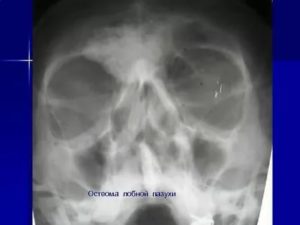

На рентгене остеома лобной пазухи выглядит как затенённое плотное пятно правильной формы.

Остеома лобной пазухи диагностируется во время рентгенологического исследования. Других эффективных методов выявить патологию на данный момент не существует.

- Рентген позволяет исследовать скелет головы и определить локализацию новообразования.